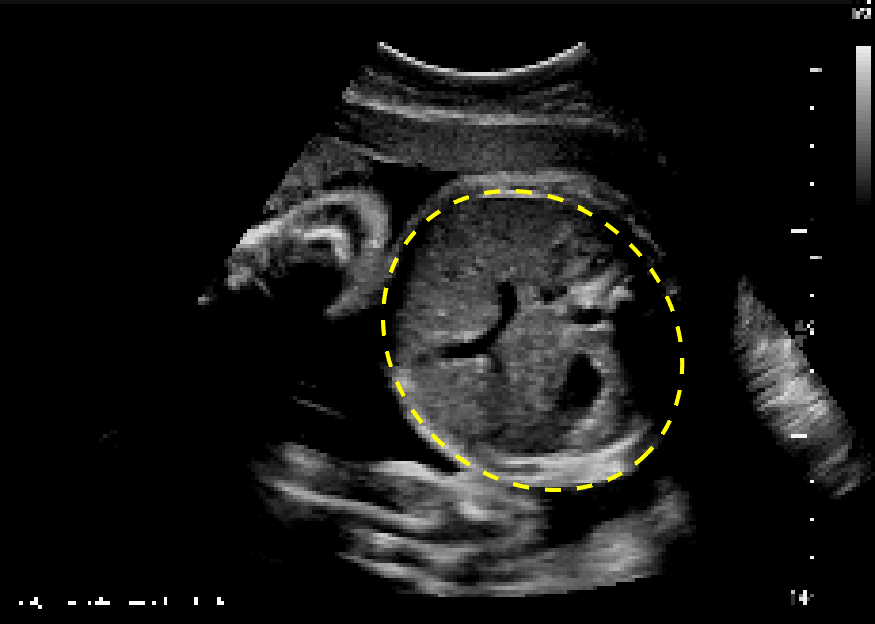

US abdominal circumference (AC) plane. Download Scientific Diagram What Causes Small Abdominal Circumference In Fetus This would happen if an ultrasound. Previous studies have suggested using fetal abdominal circumference (ac) <5%tile may be a superior measurement in predicting small for. Being one of a twin or triplets. Babies are diagnosed with intrauterine growth restriction (iugr) if they appear to be smaller than expected. Birth defects, such as heart defects. The most common causes of fgr. What Causes Small Abdominal Circumference In Fetus.